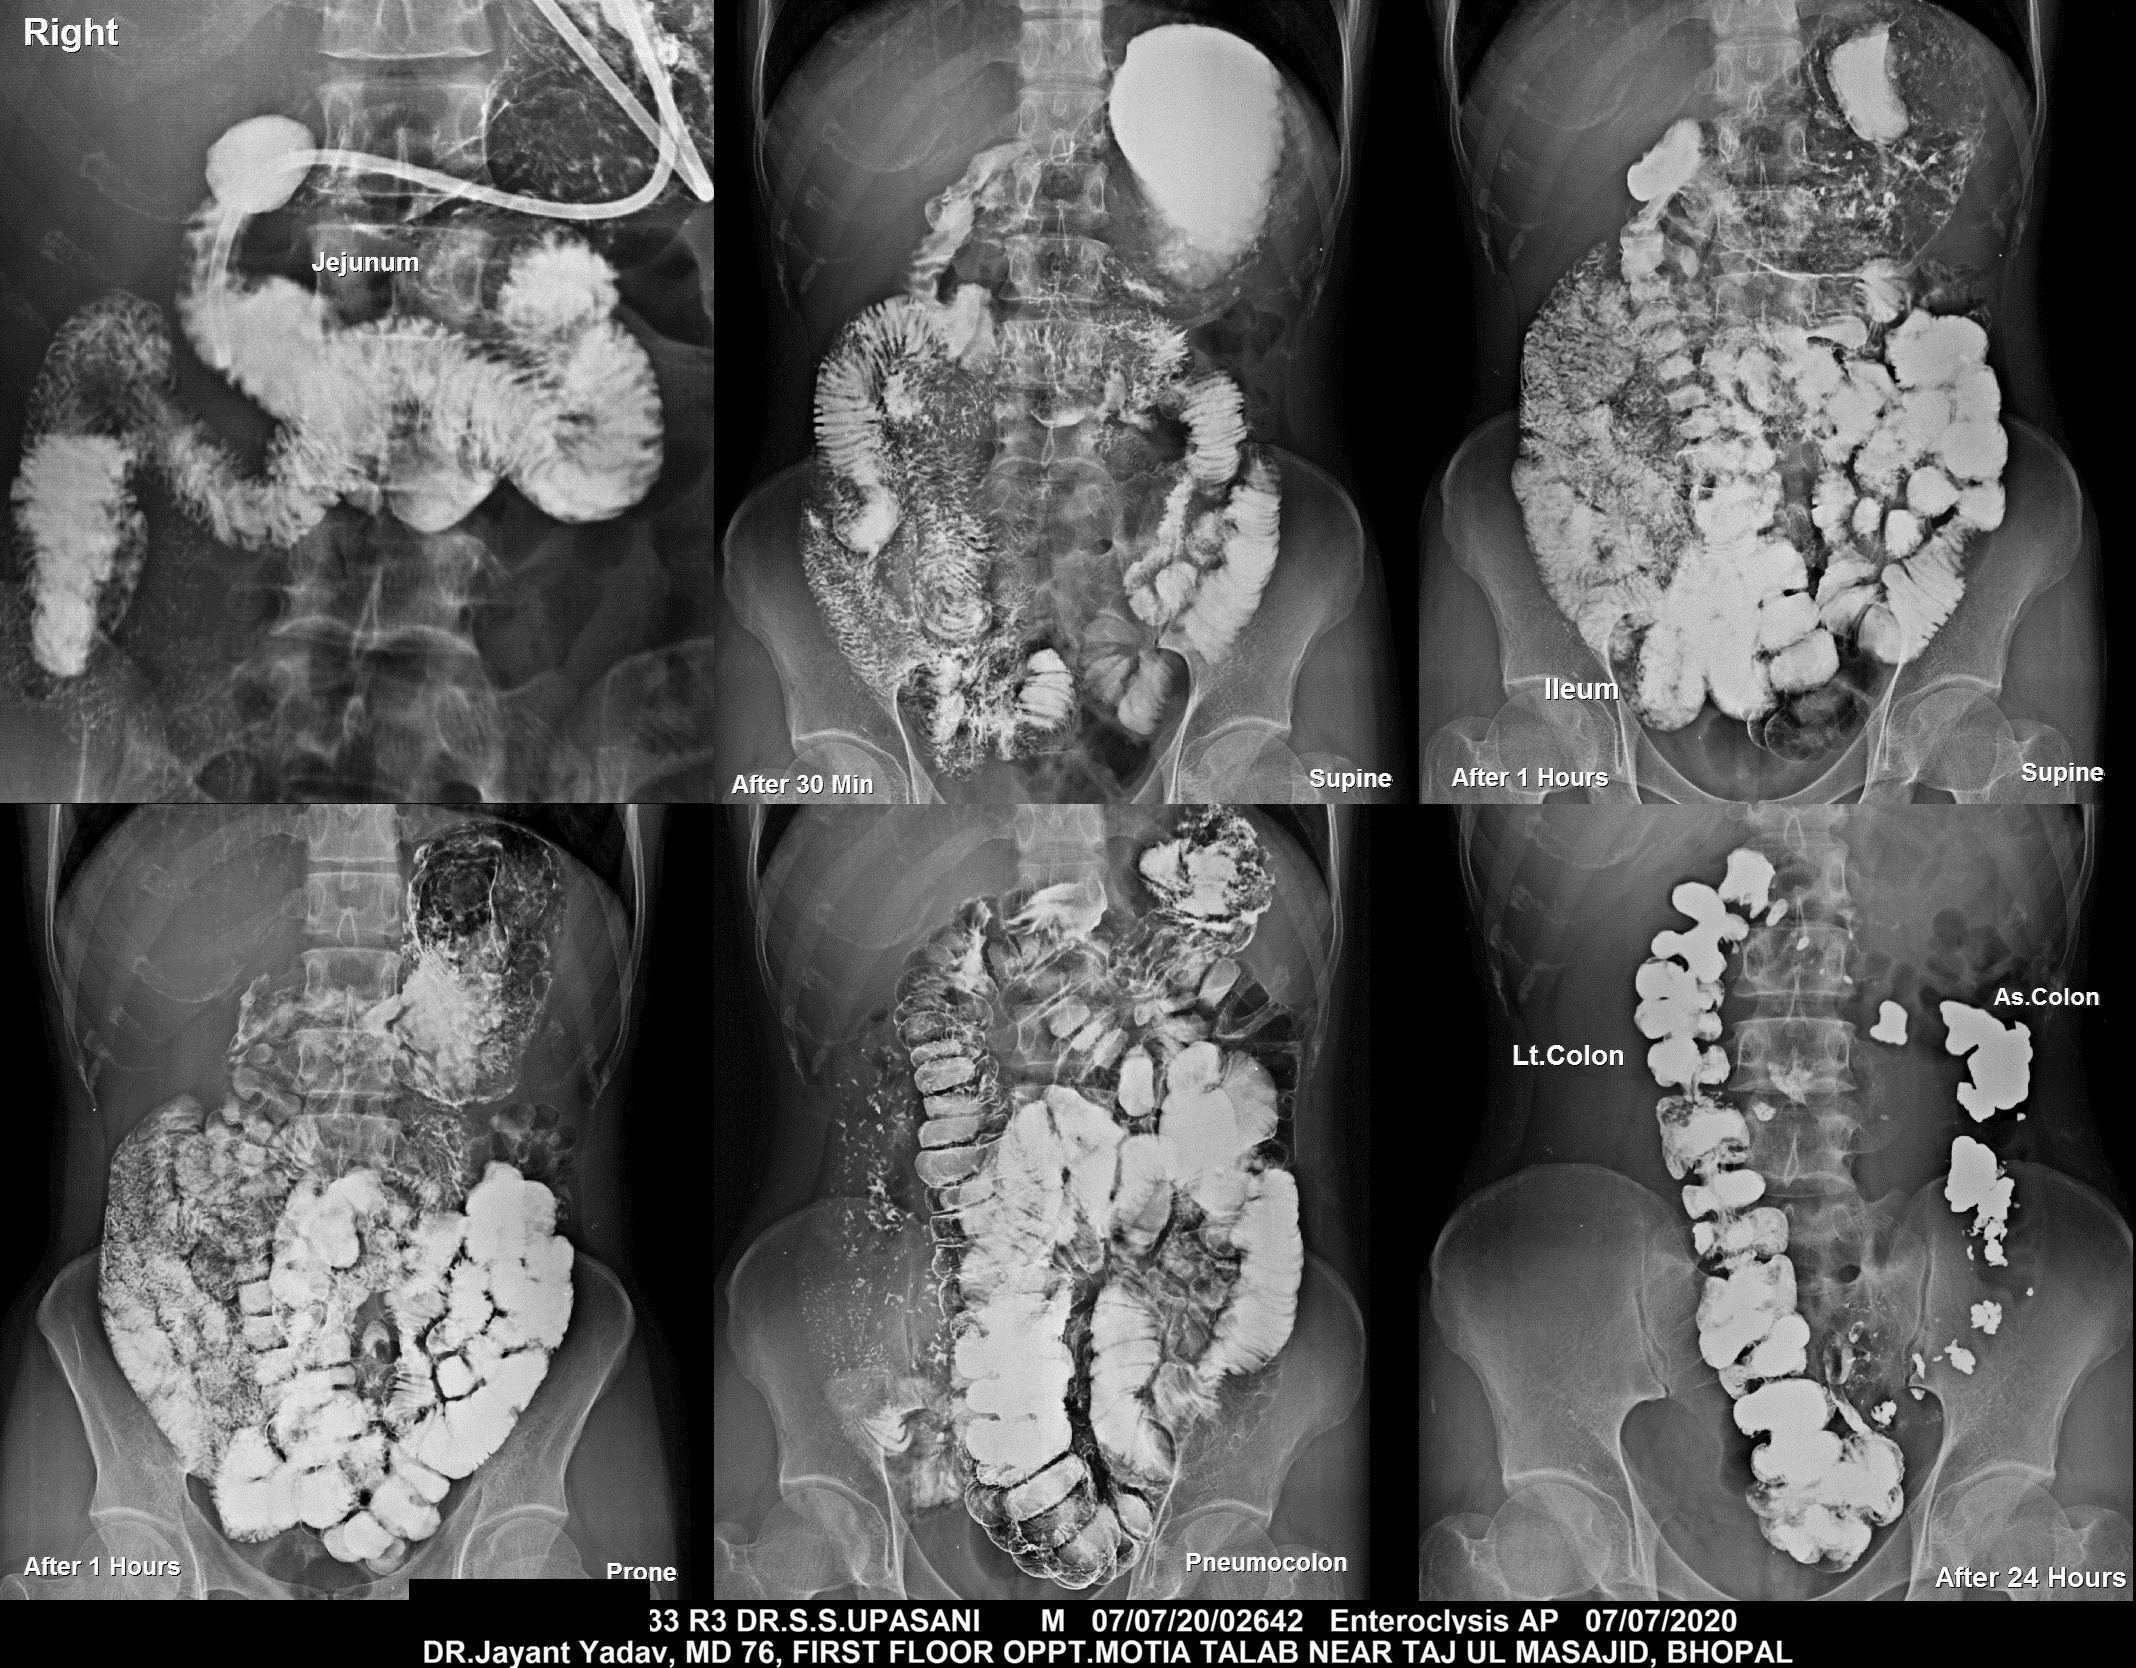

Section: ENTEROCLYSIS Total: 205 images

BaM Enteroclysis Loopogram BaE Fistulogram Urethrogram HSG